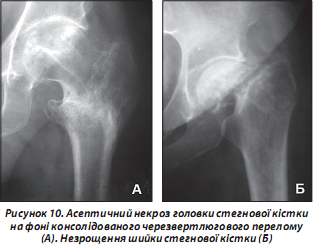

Переломи проксимального відділу стегнової кістки не завжди успішно зростаються. Це також залежить від адекватності діагностичних та лікувальних заходів, вчасності виконання хірургічного втручання, допущених тактичних та технічних помилок протягом лікувально-реабілітаційного періоду. Навіть після вдало проведеного хірургічного втручання можуть виникнути як ранні ускладнення, що загрожують життю літньої людини, так і пізні — у формі асептичних некрозів головки (рис. 10А) або незрощення шийки стегнової кістки (рис. 10Б).